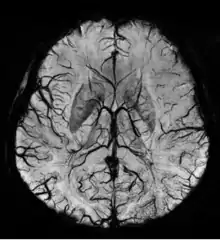

An SWI venogram of a neonate with Sturge-Weber syndrome who did not display neurological symptoms is shown to the right. The initial conventional MR imaging methods did not demonstrate any abnormality. The abnormal venous vasculature in the left occipital lobe extending between the posterior horn of the ventricle and the cortical surface is clearly visible in the venogram. Due to the high resolution even collaterals can be resolved.